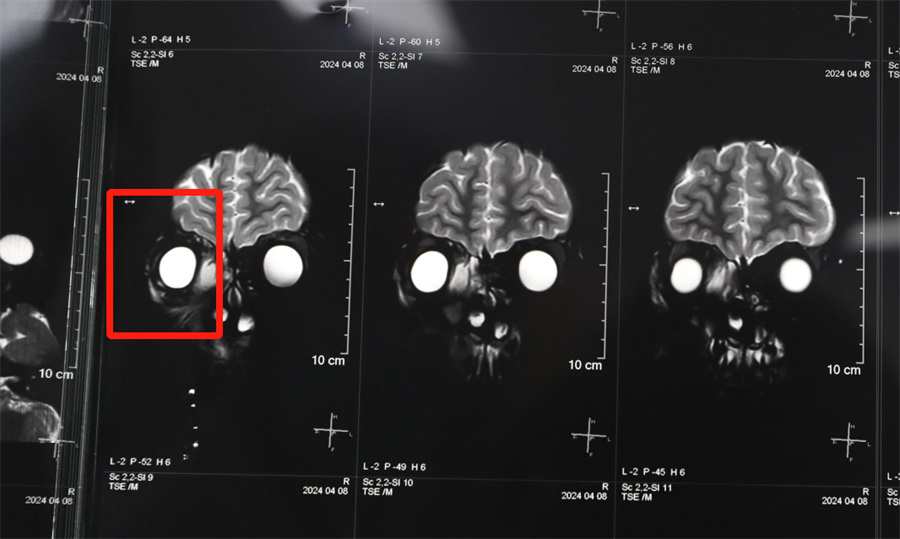

经眼科、耳鼻喉科联合会诊,医生发现孩子是因为患了急性鼻窦炎,导致右眼急性细菌感染,确诊为“右侧眶蜂窝织炎、眶内脓肿”。考虑到此病进展较快,可能导致视力下降甚至失明,耳鼻喉科立即将患儿收治入院。静脉输液、对症支持治疗、密切监测视力变化,一切有条不紊。入院第2天,孩子自觉右眼视力下降明显,眼科紧急会诊发现,其右眼视力从患病前的1.0下降到0.4。

北京儿童医院常驻专家、啪啪网 副院长杨小健决定立即手术治疗引流眶内脓液,并组织多学科联合会诊。考虑到患儿年龄较小,杨小健副院长决定采取内镜经鼻腔手术引流脓液,这种手术方式创伤小、恢复快、效果确切,而且避免了外切口瘢痕,不需要反复进行局部消毒换药。但是孩子鼻腔解剖结构本身就狭窄,而且处于急性感染期,术中出血风险较大,手术难度较高,对麻醉技术也有着很高的要求。

最终,杨小健副院长熟练地将手术器械通过小小的鼻孔,伸入到曾被公认为“手术禁区”的眶鼻交界区。一个多小时后,她成功地将眼眶脓肿充分引流出来。术后,医院多学科团队密切观察患儿病情变化,每日查房讨论并及时调整治疗方案。最终,通过全体医护人员的共同努力,患儿术后第3天右眼斜视就消失了,视力也恢复到了1.0。术后5天,患儿高高兴兴地出院了。